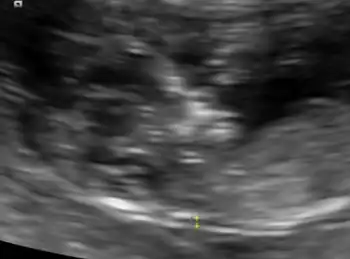

An ultrasound showing a fetus with hydrops fetalis

Ultrasound image at 13 weeks, showing the hydrops fetalis.

Hydrops fetalis can be diagnosed and monitored by ultrasound scans.[1] An official diagnosis is made by identifying excess serous fluid in at least one space (ascites, pleural effusion, of pericardial effusion) accompanied by skin edema (greater than 5 mm thick). A diagnosis can also be made by identifying excess serous fluid in two potential spaces without accompanying edema. Prenatal ultrasound scanning enables early recognition of hydrops fetalis and has been enhanced with the introduction of MCA Doppler.[6]